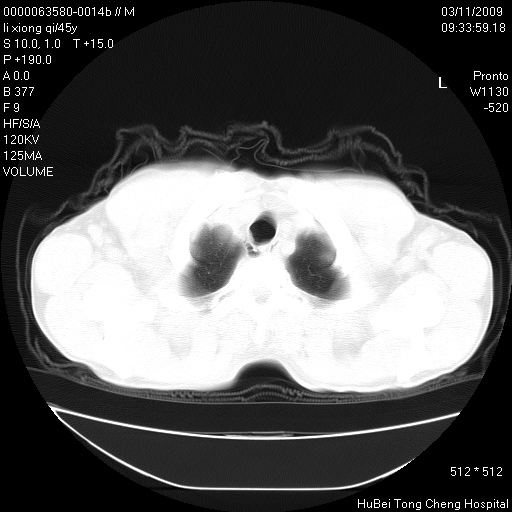

患者 男,45岁。胸痛,咳嗽伴痰中带血1月余。

临床诊断:肺结核?

胸部ct轴位平扫(层厚10mm,螺距1.5,重建间隔10mm),图像如下:

考虑肝癌肺转移